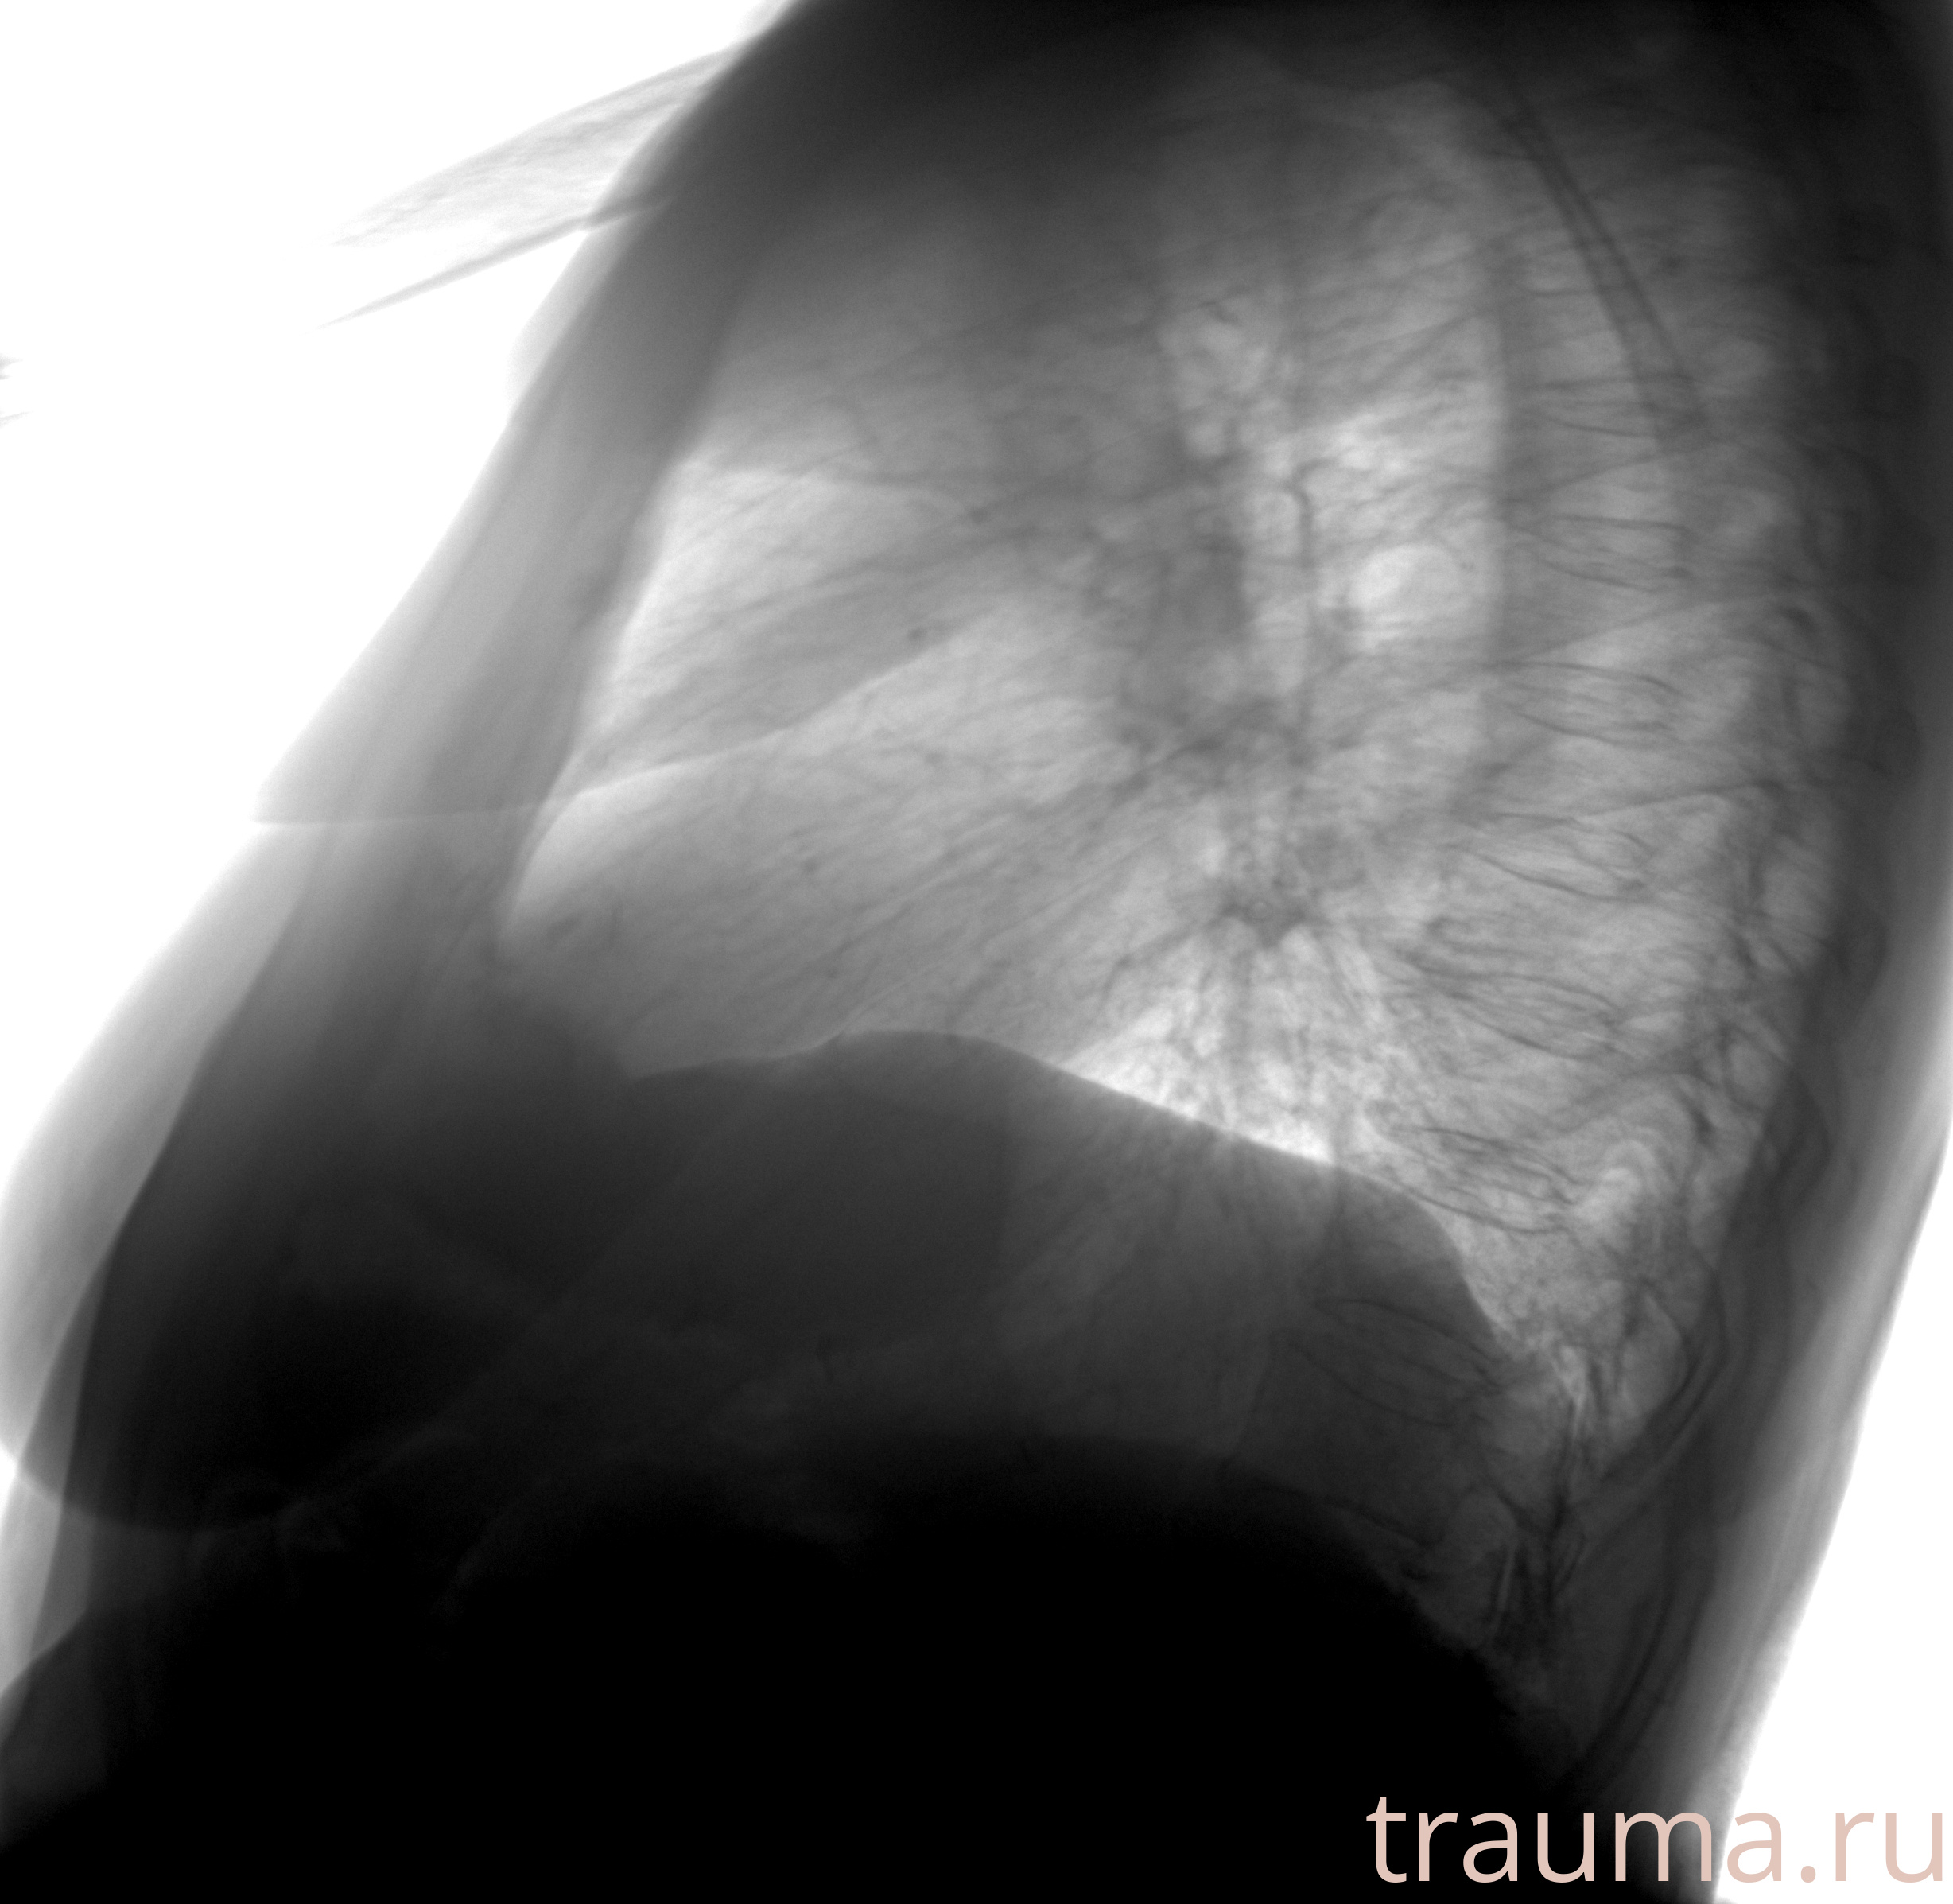

Рентгенограммы

Рентген на дому: по вашему адресу приезжает врач-рентгенолог, травматолог-ортопед с мобильным рентгеновским аппаратом, проводит диагностику травмы или заболевания, делает необходимые рентгенограммы, дает рекомендации по дальнейшему лечению. Получить качественные снимки в домашних условиях возможно благодаря уникальной методике, разработанной МосРентген Центром для института  Склифосовского

при переломе шейки бедра и пневмонии от компании МосРентген Центр - партнера Института имени Склифосовского